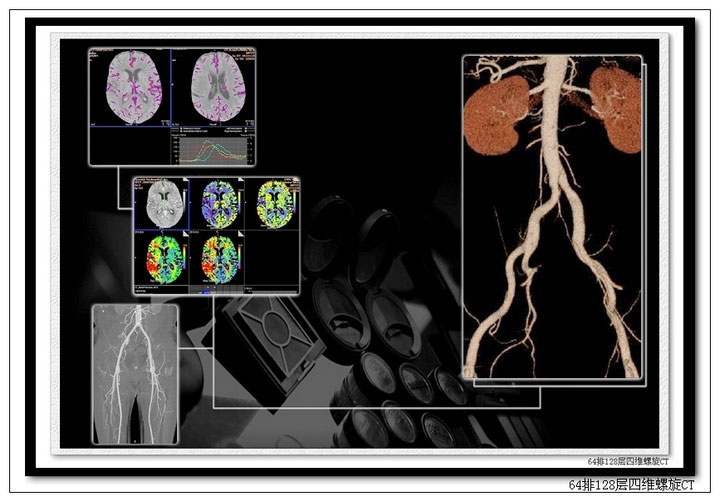

我院引进的西门子SOMATOM Definition AS+ 64排128层四维螺旋CT己投入临床运行。它是目前我市最先进、最高端的螺旋CT。该机融合了独有的银河平台,突破传统CT技术瓶颈,实现了从二维、三维成像进入四维成像的全新时代,一次扫描即可获得全时相动态血管成像,又可获得全脑、全肝脏等脏器的灌注,将对肿瘤学研究起到极大的帮助。该机超快速扫描能力,可以在几秒钟内完成从头到脚的全身高精度影像检查。应用先进的磁悬浮机架驱动及独特的零兆球管技术,达到业界最快的0.3s的机架转速,使心脏检查能力超越了任何的64层CT。由于该机器拥有多种先进技术,达到了CT扫描速度、覆盖范围、图像质量和低X线剂量的完美统一,对全身心血管系统、神经系统、急诊医学、肿瘤诊断学都具有极好的影像诊断效果。

其特殊功能具体表现在以下几个方面:1、全身血管成像: CT 血管成像(CTA)是多层螺旋CT 的一项重要应用,然而对于血管的动态成像与分析,由于连续采集技术和扫描剂量的限制涉足较少。SOMATOMDefinition AS+ 的无缝式的动态螺旋采集技术的诞生,实现血管不同期相的独立成像,增强了血管功能成像的临床应用,开创了全时相动态CTA 的新纪元。可清晰显示动脉瘤、血管畸形、血管狭窄、动脉粥样硬化斑块、血管闭塞、主动脉夹层、肿瘤增生血管等。2、心脏冠状动脉成像和心功能评价:由于采用磁悬浮驱动技术与轻量化球管,实现了0.30 秒的旋转速度,3-5秒完成对于整个心脏高分辨率扫描,使得冠状动脉检查成功率接近100%,在冠状动脉血管病变的筛查、冠状动脉支架和搭桥血管评价等方面极具优势。另外利用心脏功能软件,还可以对某些心脏功能指标进行评价。3、CT灌注成像:CT灌注是指在静脉注射对比剂的同时,对选定的层面进行连续多次扫描,以获得每一像素的时间-密度曲线,计算出灌注组织的血流量、血容量、平均通过时间及毛细血管通透性等指标。除了对早期脑梗塞作出准确诊断外,对常规CT扫描和增强扫描时不易鉴别的肿瘤、炎症的鉴别诊断能够提供更有意义的依据,以及对治疗效果做出评价。4、急诊检查:对于急性胸痛患者,可进行一次快速、非侵入式扫描,就能诊断出是否有心脏疾病、肺栓塞或者主动脉夹层三大主要导致胸痛的最致命性原因。对于外伤患者,通过短短10秒钟的扫描和先进的后处理软件能够对脏器的损伤和骨折做出及时诊断,为临床抢救赢得了时间,而且也节约了检查费用。5、先进的仿真内镜技术:可应用于胃肠首、血管、气管、支气管、胆道、输尿管等空腔脏器的仿真内镜检查,大大提高了病变的检出率和诊断的准确性。 6、肺功能检查与肺结节分析:分别于深吸气末及深呼气末对肺进行CT扫描,在工作站可快速准确地测定患者的各项肺功能指标,对慢性阻塞性肺疾病患者肺通气功能的评价具有重要的临床意义。应用计算机辅助诊断,自动分析和记录首次检查的结果,再次复查时可自动计算出肺结节的增长率和倍增时间,为判断结节的良恶性提供客观依据。7、超越扫描范围的全剂量调控